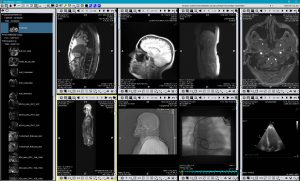

TM-PACS

Lets you compress, secure, store, and view x-ray images using cutting-edge display and viewing tools (zoom, magnifier, annotations, distance measurement, measurement tracking, etc.). The user can view coronarographic, PET, and nuclear medicine images at the same time, as well as more classic imaging (MRI, CT scan, ultrasound, etc.). The use of labels associated with the exams lets you create groups of exams and access them via one click. A personalised search system allows you to access the desired patient file or exam very quickly. The display is optimised to allow multi-screen display, as well as the integration of the RIS and PACS software installed on the same diagnostic stations.